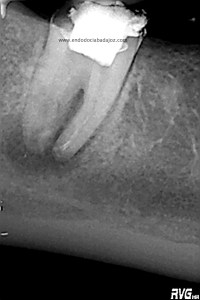

Con ayuda del microscopio, pudimos confirmar que se trataba de una reabsorción interna en el tercio medio y una reabsorción radicular del conducto distal.

Bueno, pues el conducto distal se obturó en su tercio apical y medio con M.TA.

Hemos llamado a revisión a la paciente en varias ocasiones ( 6 meses y 9 meses)

(revision a los 6 meses) (revisión a los 9 meses)

Como podemos observar, la lesión periapical ha regenarado: